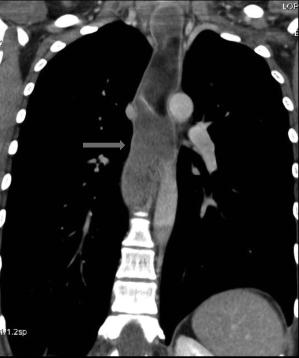

A etat tardive oesophage dilate et

alonge en forme de petit chaussette . |